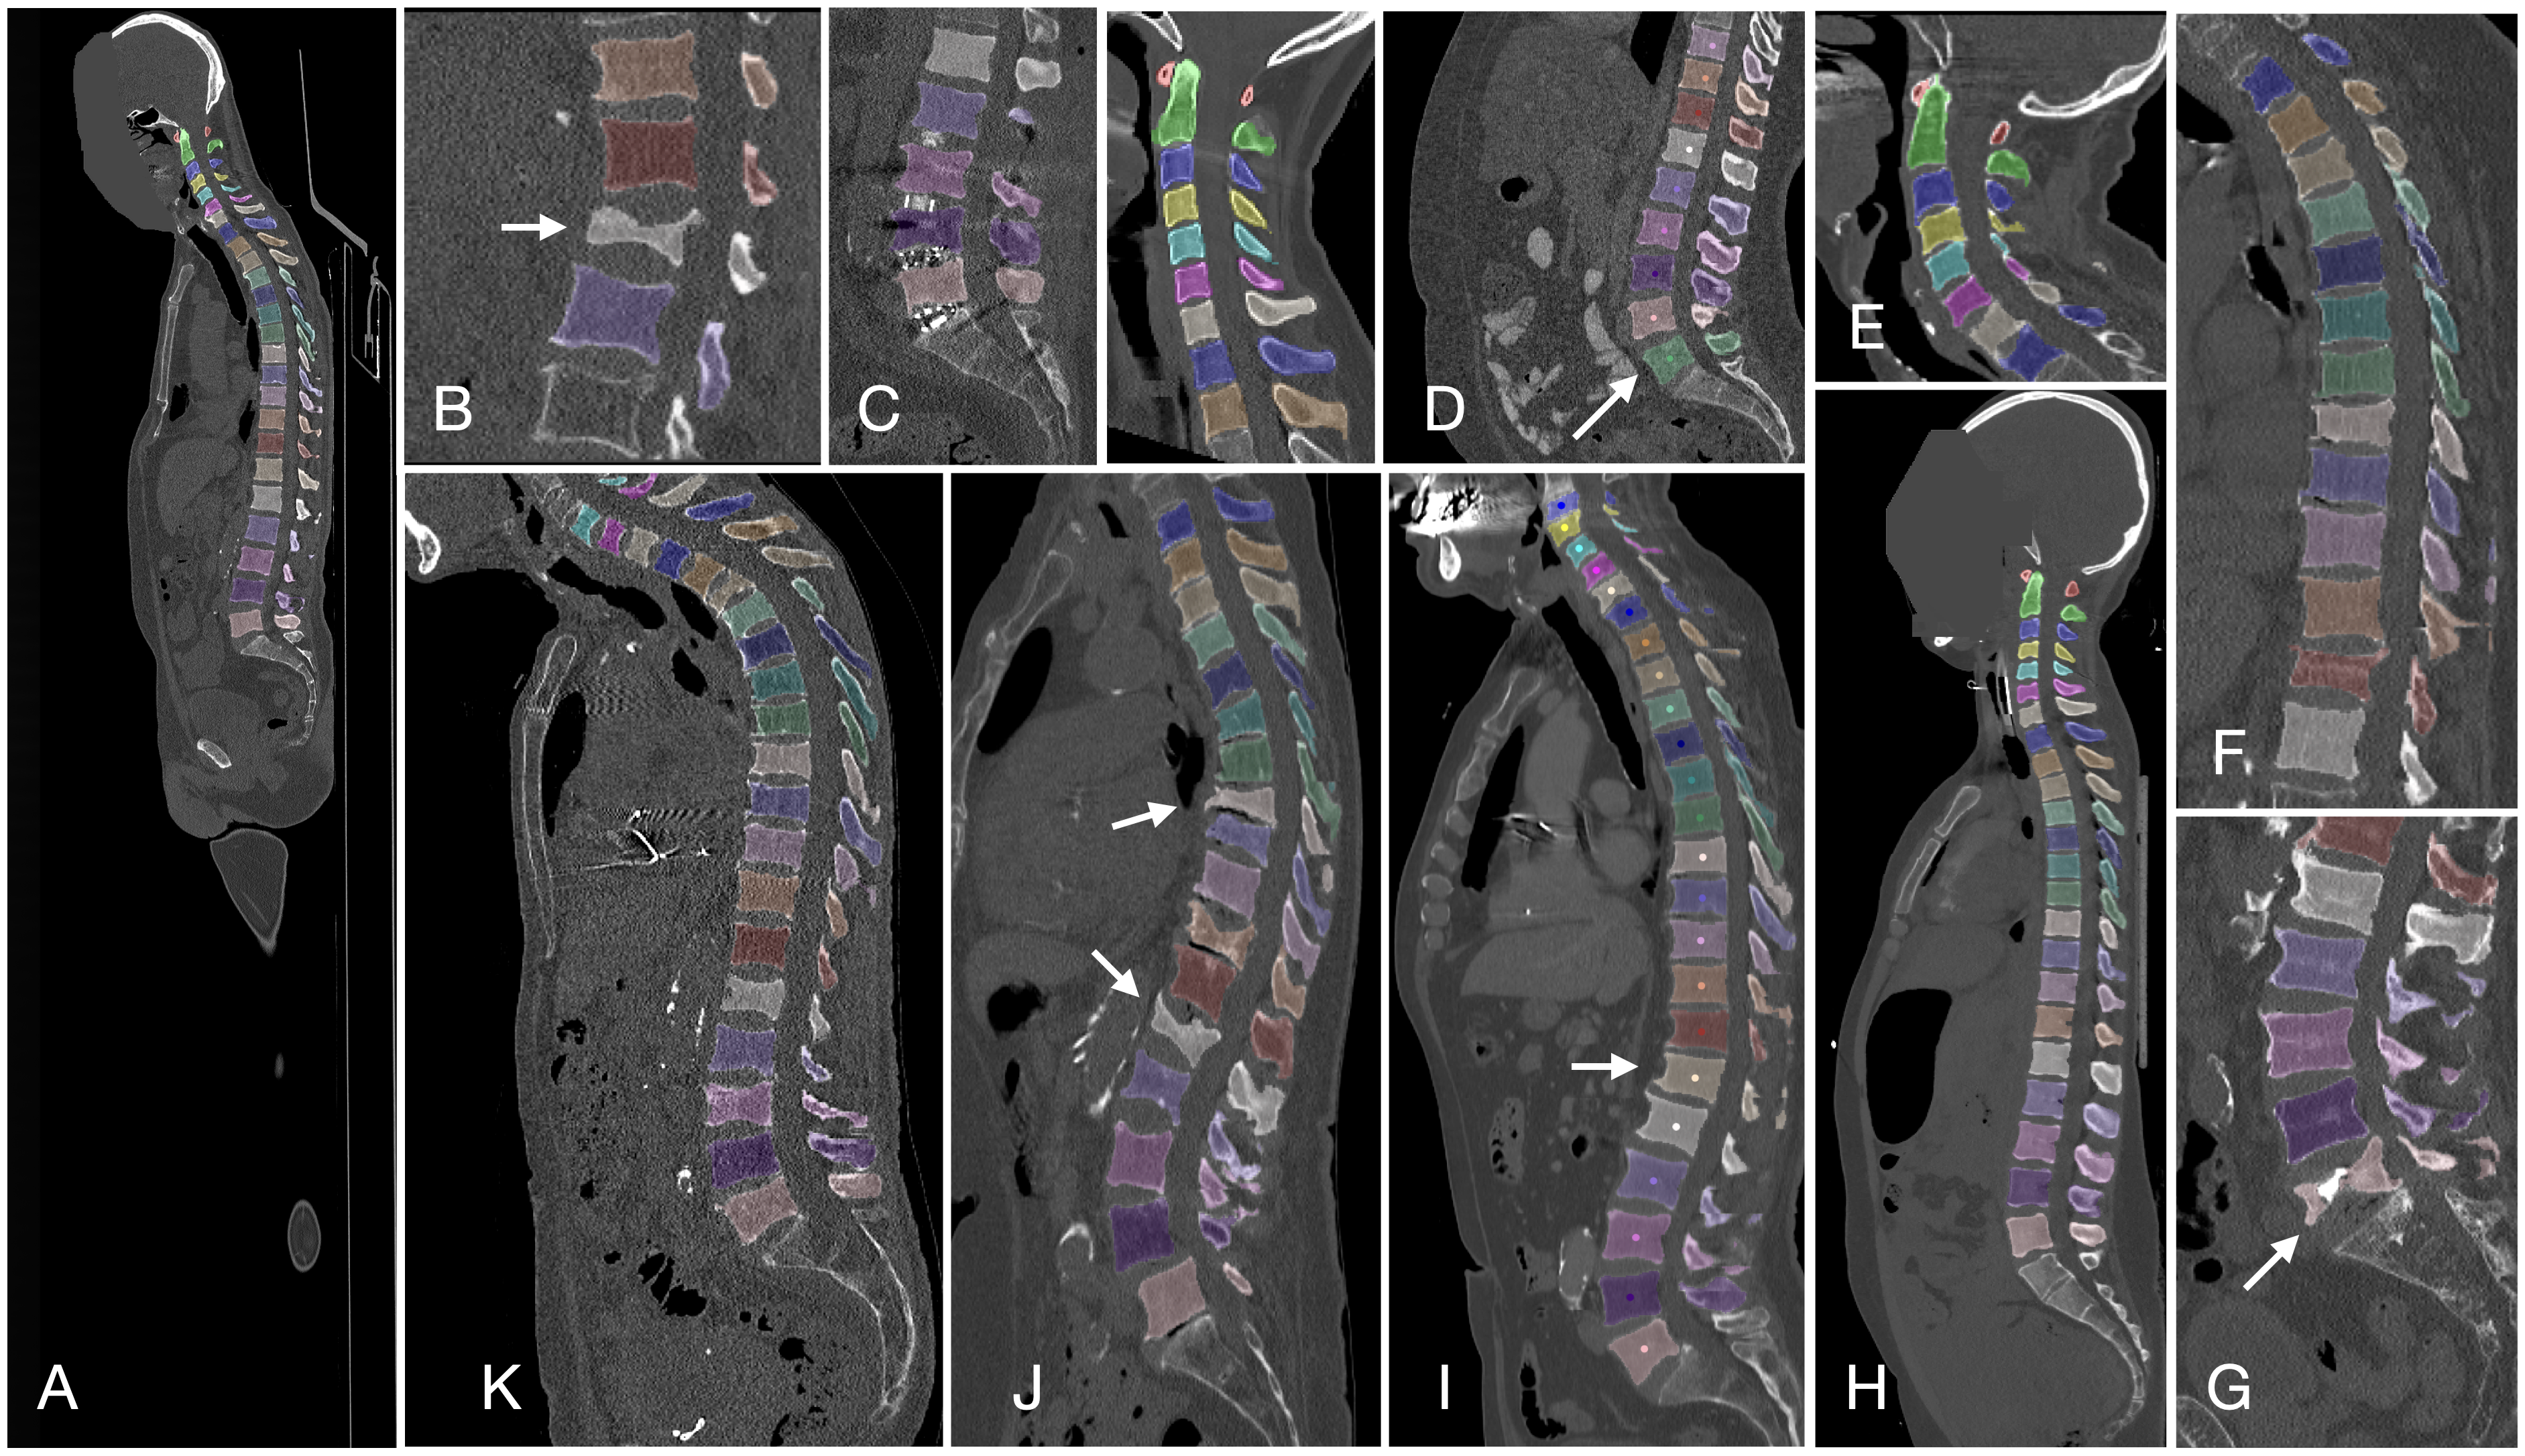

脊椎

Verse大规模脊椎分割数据集

| VerSe | 脊椎 | 分割 | CC BY-SA 4.0 |